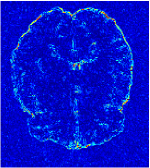

All the experiments are implemented on a Windows workstation with Intel Core i9 CPU at 3.3GHz and an Nvidia GTX-1080Ti GPU with 11GB of graphics card memory via TensorFlow Abadi et al. (2016). The parameters in the proposed network are initialized by using Xavier initialization Glorot and Bengio (2010). We trained the meta-learning network with four tasks synergistically associated with four different CS ratios: 10%, 20%, 30%, and 40%, and test the well-trained model on the testing dataset with the same masks of these four ratios. We have 300 training data for each CS ratio, which amount to total of 1200 images in the training dataset. The results for and MR reconstructions are shown in Tables 5.4 and 5.4 respectively. The associated reconstructed images are displayed in Figures 1 and 3. We also test the well-trained meta-learning model on unseen tasks with radio masks for skewed ratios: 15%, 25%, 35%, and random Cartesian masks with ratios 10%, 20%, 30% and 40%. The task-specific parameter for the unseen tasks are retrained for different masks with different sampling ratios individually with fixed task-invariant parameters . In this experiments, we only need to learn for three skewed CS ratios with radio mask and four regular CS ratios with Cartesian masks. The experimental training proceed on less data and iterations, where we performed on 100 MR images with 50 epochs. For example, for reconstructing MR images with CS ratio 15% radio mask, we fix the parameter and retrain the task-specific parameter on 100 raw data with 50 epochs, then test with renewed on our testing data set with raw measurement that sampled from radio mask with CS ratio 15%. The results associated with radio masks are shown in Table 5.4 and 5.4, Figure 2 and 4 for and images respectively. The results associated with Cartesian masks are list in Table 5.4 and reconstructed images are displayed in Figure 5.

Qualitative comparison between conventional and Meta-learning methods are shown in Figure 1 and 3, which display the reconstructed MR images of the same slice for T1 and T2 respectively, we label the zoomed-in details of HGG in the red boxes. We observe the evidence that conventional learning is more blurry and lost sharp edges, especially in lower CS ratios. From the point-wise error map, we find meta-learning has the ability to reduce noises especially in some detailed and complicated regions comparing to conventional learning.